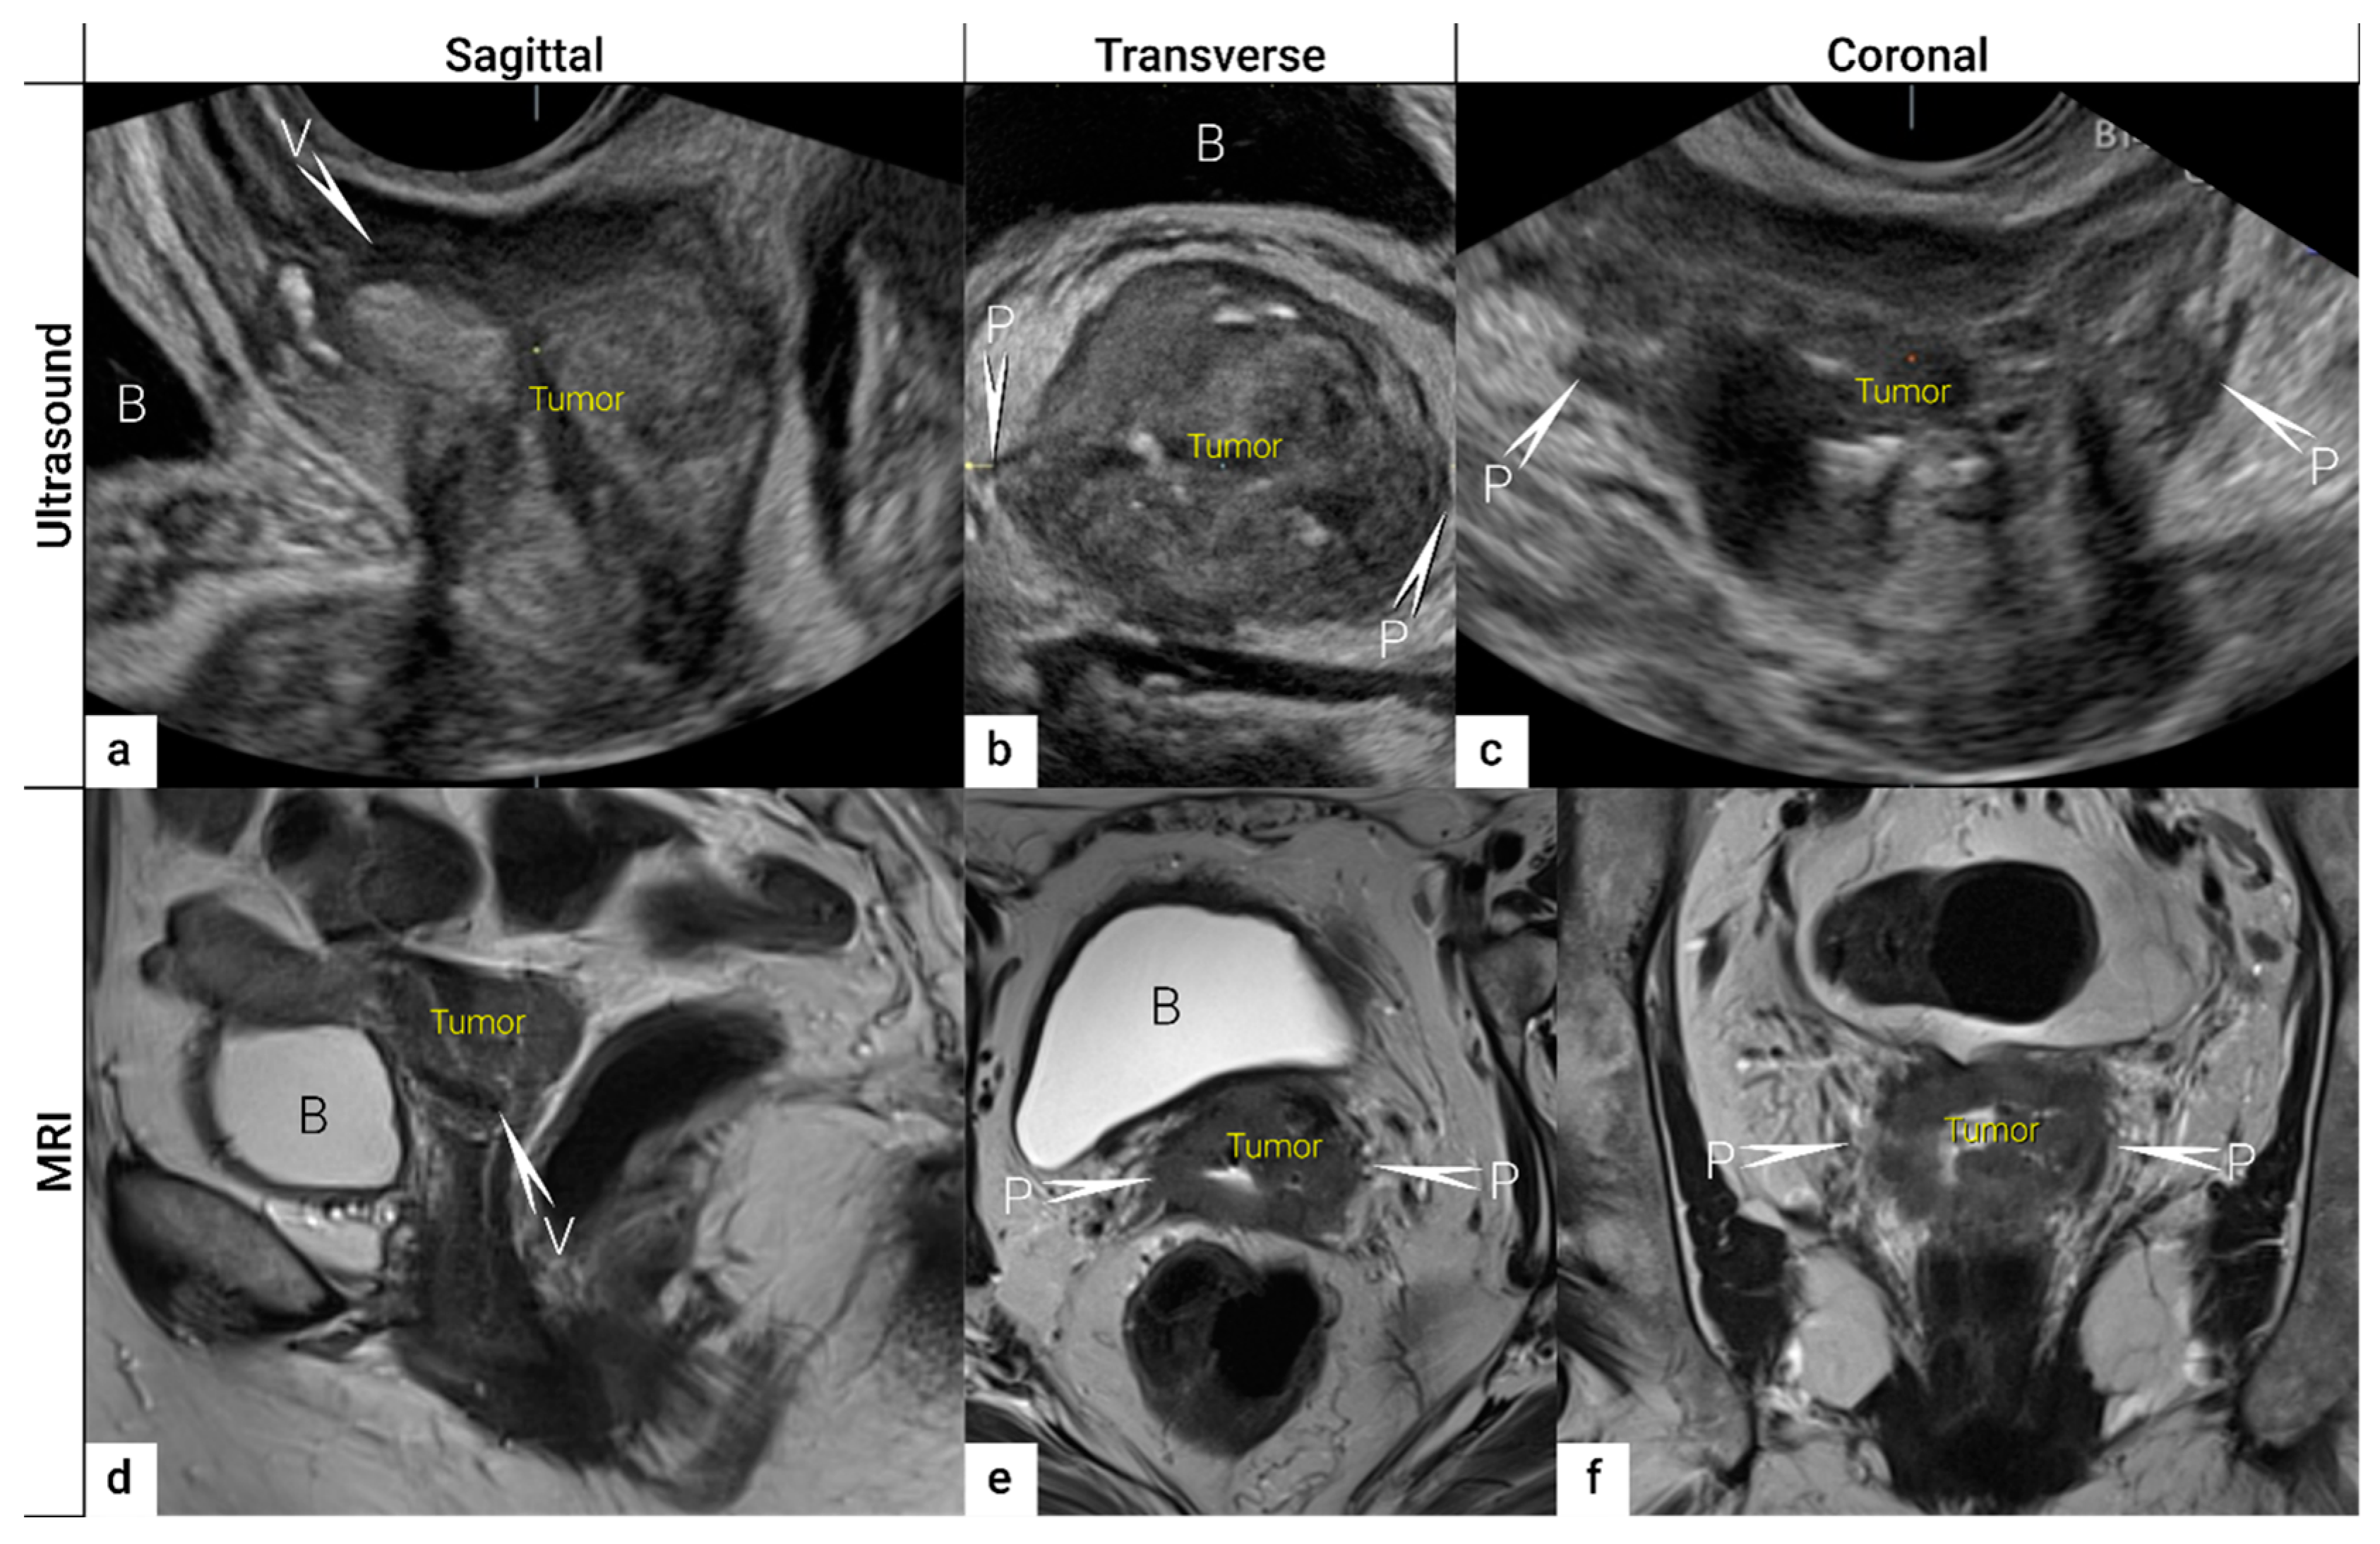

3.2. Tumour Delineation within Cervix (Tumour Size, Depth of Stromal Invasion, Minimum of Uninvolved Stroma, and Cranial Tumour-Free Margin)

| IB | Carcinoma with deepest stromal invasion >5 mm, limited to the cervix uteri with size measured by maximum tumour diameter. | US: Highly vascularised hypoechogenic (squamous-cell carcinoma) or iso-/hyperechogenic lesion (adenocarcinoma) with intact hyperechogenic pericervical fascia and positive sliding sign between tumour and bladder/rectum. MRI: Tumour has intermediate to high signal on T2W images. Dynamic CE-T1W images depicts tumour as hyperintense in the arterial phase and iso- or hypointense in the venous phase. Tumours characteristically exhibit restricted diffusion on DWI (hyperintensity on high b-value images and low intensity on the ADC maps). Tumour does not disrupt the hypointense peripheral stromal ring (best seen on T2W images). | |

| T2b | IIB | Parametrial tumour invasion but no pelvic side wall extension | US: Tumour infiltrates the hyperechogenic pericervical fascia, negative sliding sign, presence of hypoechogenic tumour projections into hyperechogenic parametria. MRI: Tumour disrupts the hypointense peripheral stroma and extends into the parametrium +/− abutting parametrial vessels on T2W images. |